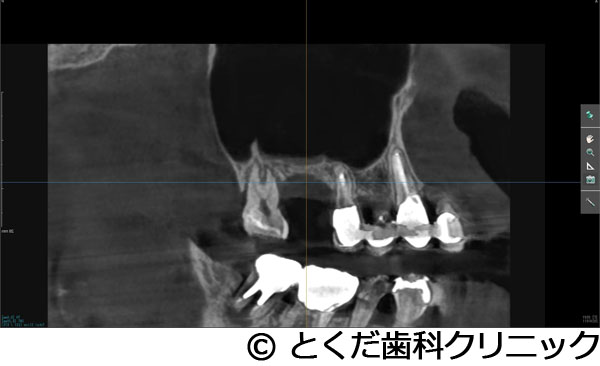

¡Ú¾ÉÎã4¡Ûº¸¾å4È֤ϥ¤¥ó¥×¥é¥ó¥ÈÈ´»õ¨»þËäÆþ¡¢º¸¾å6È֤Ͼå³Ü´û¸¹ü1¡Á2mm¤Î¥±¡¼¥¹¤Ç¥°¥é¥Õ¥È¥ì¥¹¥µ¥¤¥Ê¥¹¥ê¥Õ¥È¤ò»Ü¹Ô º¸²¼56¤Ï·ç»¤¬Â礤¯¡¢²¼³Ü¿À·Ð¤Þ¤Ç¤Îµ÷Î¥¤¬¤Ê¤¤¥±¡¼¥¹¤Ç¡¢²¼»õÁå´ÉËãáã¤ò²óÈò¤¹¤ë¤¿¤á¤Ë¥·¥ç¡¼¥È¥¤¥ó¥×¥é¥ó¥È¤ò»ÈÍÑ ºÇ½ªÊäÄÖʪ¤Ïº¸¾å456¤Î3¥æ¥Ë¥Ã¥È¤Î¥¸¥ë¥³¥Ë¥¢¥Ö¥ê¥Ã¥¸¡¢º¸²¼56¤Ï¥¸¥ë¥³¥Ë¥¢¤ÎÏ¢·ë´§¤òÁõÃ夷¤¿¥±¡¼¥¹

- º¸¾å4È֤ϥ¤¥ó¥×¥é¥ó¥ÈÈ´»õ¨»þËäÆþ¡¢º¸¾å6È֤Ͼå³Ü´û¸¹ü1¡Á2mm¤Î¥±¡¼¥¹¤Ç¥°¥é¥Õ¥È¥ì¥¹¥µ¥¤¥Ê¥¹¥ê¥Õ¥È¤ò»Ü¹Ô º¸²¼56¤Ï·ç»¤¬Â礤¯¡¢²¼³Ü¿À·Ð¤Þ¤Ç¤Îµ÷Î¥¤¬¤Ê¤¤¥±¡¼¥¹¤Ç¡¢²¼»õÁå´ÉËãáã¤ò²óÈò¤¹¤ë¤¿¤á¤Ë¥·¥ç¡¼¥È¥¤¥ó¥×¥é¥ó¥È¤ò»ÈÍÑ ºÇ½ªÊäÄÖʪ¤Ïº¸¾å456¤Î3¥æ¥Ë¥Ã¥È¤Î¥¸¥ë¥³¥Ë¥¢¥Ö¥ê¥Ã¥¸¡¢º¸²¼56¤Ï¥¸¥ë¥³¥Ë¥¢¤ÎÏ¢·ë´§¤òÁõÃ夷¤¿¥±¡¼¥¹

º¸²¼56¤Ï¡¢»õ¼þɤÇÂ礤ʹü·ç»¤òȼ¤Ã¤Æ¤¤¤¿¡£º¸¾å456¤Ë´Ø¤·¤Æ¤Ï¡¢Æ°Íɤ¬Â礤¯±ê¾É¤¬µ¯¤¡¢ÇÓÇ¿¤ª¤è¤Ó»õÀ¾å³Üƶ±ê¤òµ¯¤³¤·¤Æ¤¤¤¿¡£

¼£ÎÅÊýË¡

´µ¼ÔÍͤϺ¸¾å¤ÎưÍɤ¬º¸¾å56¤ÎÈ´»õ¤ò´õ˾¡£¤½¤Î¸å¡¢¥¤¥ó¥×¥é¥ó¥È¼£ÎŤò´õ˾¤·¤¿¤¿¤áº¸¾å4¤Ë´Ø¤·¤Æ¤ÏÈ´»õ¨»þËäÆþ¡£º¸¾å6¤Ë´Ø¤·¤Æ¤Ï¡¢´û¸¹ü1¡Á2mm¤Ç¥¤¥ó¥×¥é¥ó¥È¼£ÎŤ¬¸·¤·¤¤¾õÂ֤Ǥ¢¤Ã¤¿¤¬¡¢¥°¥é¥Õ¥È¥ì¥¹¥µ¥¤¥Ê¥¹¥ê¥Õ¥È¤Ç¥¤¥ó¥×¥é¥ó¥ÈËäÆþ¤ò¹Ô¤¤¤Þ¤·¤¿¡£¤½¤Î¸å¡¢2¥õ·îȾ¸å¡¢ÂçÉý¤Ë¹ü¤¬·ç»¤·¤Æ¤¤¤ë²¼³Ü56¤ËÂФ·¤Æ¥·¥ç¡¼¥È¥¤¥ó¥×¥é¥ó¥È¤ò»ÈÍѤ·¤Æ¡¢²¼³Ü¿À·Ð¤Î»½ý¤òÈò¤±¤Æ¥¤¥ó¥×¥é¥ó¥ÈËäÆþ¤Î¼ê½Ñ¤ò½ª¤¨¤Æ¤¤¤Þ¤¹¡£¤½¤Î¸å2¥õ·î¸å¤Ë¸÷³Ø°õ¾Ý¤Ç°õ¾Ý¤ò¹Ô¤¤¡¢º¸¾å456¤Ï3¥æ¥Ë¥Ã¥È¤Î¥¸¥ë¥³¥Ë¥¢¥Ö¥ê¥Ã¥¸¤òÁõÃå¡£²¼º¸56¤Ë´Ø¤·¤Æ¤Ï¹ü·ç»¤¬Â礤¤¤¿¤á¡¢»õ´§Ä¹¤¬¤À¤¤¤ÖŤ¯¤Ê¤ë¤¿¤á¡¢¥¸¥ë¥³¥Ë¥¢¤ÎÏ¢·ë´§¤òÁõÃ夷¤Æ¼£ÎŤò½ª¤¨¤Æ¤¤¤Þ¤¹¡£

¾å³Ü6¤Ë´Ø¤·¤Æ¤Ï´û¸¹ü¤¬¾¯¤Ê¤¯¡¢¸·¤·¤¤¼£ÎŤǤϤ¢¤ê¤Þ¤·¤¿¤¬¡¢5¥õ·î¤Ç¼£ÎŤò½ª¤¨¡¢´µ¼ÔÍͤοÈÂÎŪ¡¢»þ´ÖŪ¡¢ÈñÍÑŪÉéô¤òºÇ¾®¸Â¤ËÍÞ¤¨¤ë¤³¤È¤¬¤Ç¤¤¿¤È¹Í¤¨¤Þ¤¹¡ÊÄ̾ï¤À¤È¼£ÎŤ¬ÉÔ²Äǽ¤È¸À¤ï¤ì¤ë¤³¤È¤¬Â¿¤¤¥±¡¼¥¹¤À¤È¹Í¤¨¤Þ¤¹¡£¤Ç¤¤¿¾ì¹ç¤â¡¢½¾Íè¤Î¥µ¥¤¥Ê¥¹¥ê¥Õ¥È¤ò¹Ô¤¤¡¢1ǯ°Ê¾å¤«1Ç¯ÄøÅ٤μ£ÎÅ´ü´Ö¤¬¤«¤«¤ë¤«¡¢»þ´ÖŪ¤ä¿ÈÂÎŪ¤Ë¤â¡¢¤Þ¤¿¡¢ÈñÍÑÌ̤ˤª¤¤¤Æ¤â¡¢´µ¼ÔÍͤËÉéô¤ò¤«¤±¤ë¥±¡¼¥¹¤À¤È¹Í¤¨¤Þ¤¹¡Ë¡£¤Þ¤¿¡¢²¼³Ü¤Ï¹ü·ç»¤¬Â礤¯¡¢²¼»õÁå´É¤Ø¤Î±Æ¶Á¤¬¹Í¤¨¤é¤ì¤ë¥ê¥¹¥¯¤¬¹Í¤¨¤é¤ì¤ë¥±¡¼¥¹¤Ç¤·¤¿¤¬¡¢¥·¥ç¡¼¥È¥¤¥ó¥×¥é¥ó¥È¤ò»ÈÍѤ¹¤ë¤³¤È¤Ç°ÂÁ´¤Ë¼£ÎŤò½ª¤¨¤ë¤³¤È¤¬¤Ç¤¤Þ¤·¤¿¡£